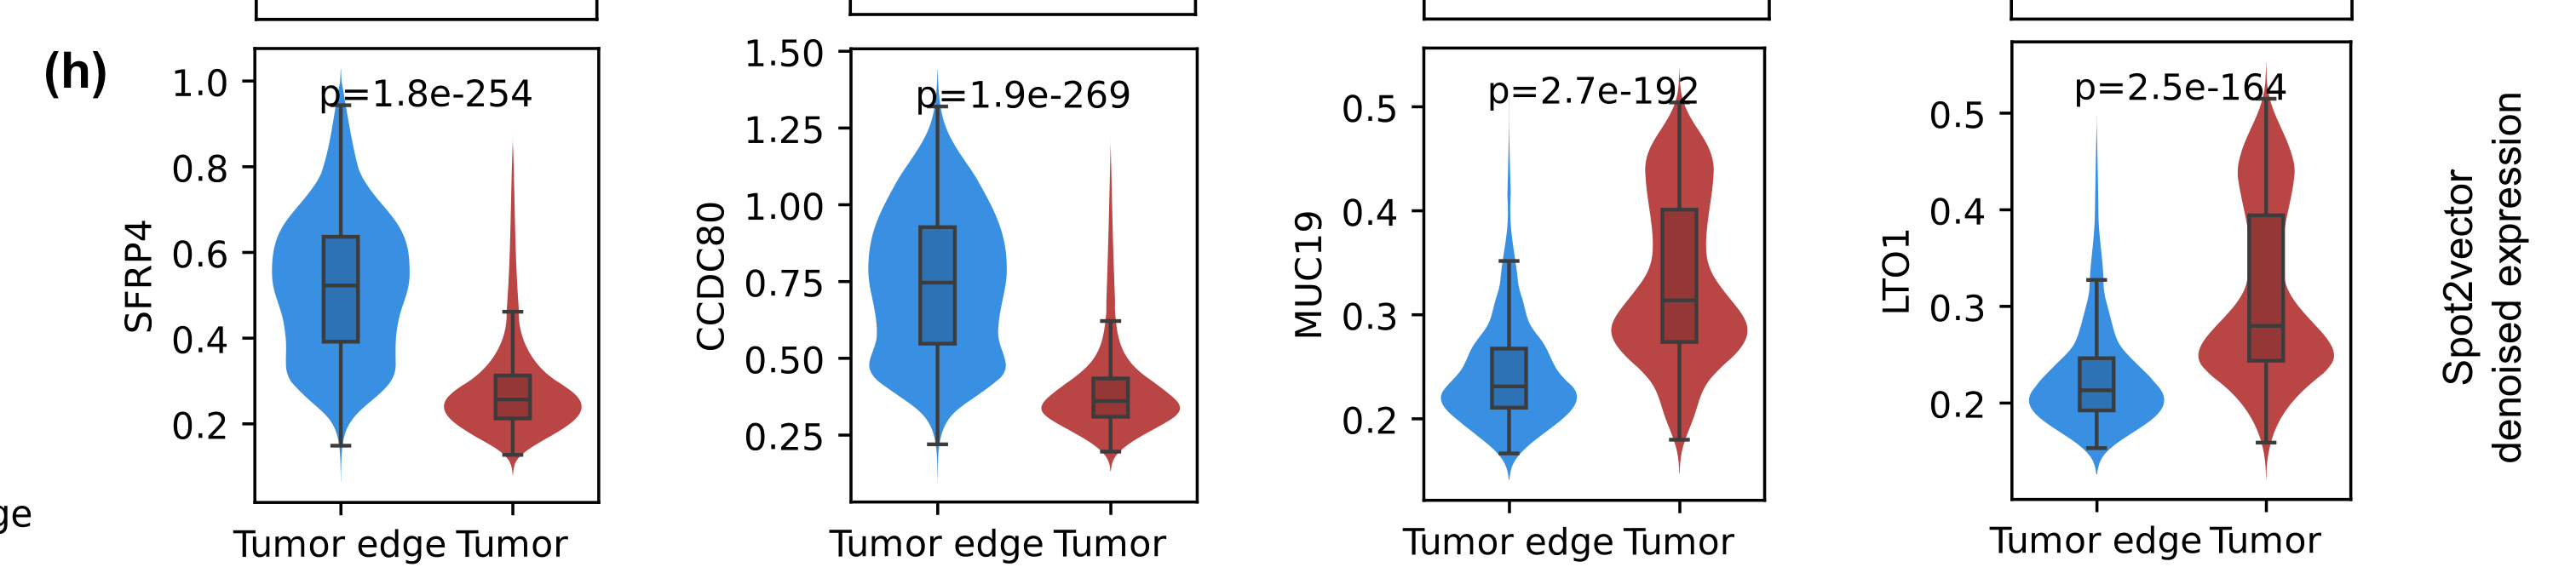

Wei R. et al. - 2022

Spatial charting of single-cell transcriptomes in tissues

Does spatial proximity to tumor cells influence the functional state of immune cells?